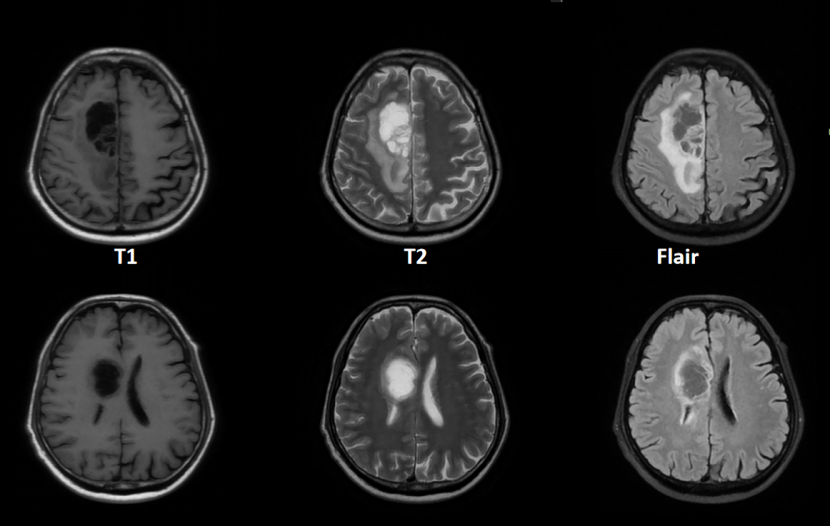

17天前,72歲的杜先生(化姓)在行膝關節(jié)手術前常規(guī)檢查時,查頭CT發(fā)現右額葉占位性病變,并于15天前出現左下肢乏力,伴思維遲鈍。MRI檢查提示為右額葉膠質瘤,這讓杜先生一家人陷入了深深的憂慮。

膠質瘤作為原發(fā)性顱腦惡性腫瘤,以其高發(fā)病率、高復發(fā)率和高死亡率著稱,治療難度極大。而杜先生的腫瘤更是棘手,因為它累及到大腦的重要功能區(qū),包括中央前回、運動前區(qū)和輔助運動區(qū)及其皮層下纖維束、大腦前動脈和大腦上靜脈等重要結構。稍有不慎,就可能造成不可逆的神經損傷。

患者術前核磁影像